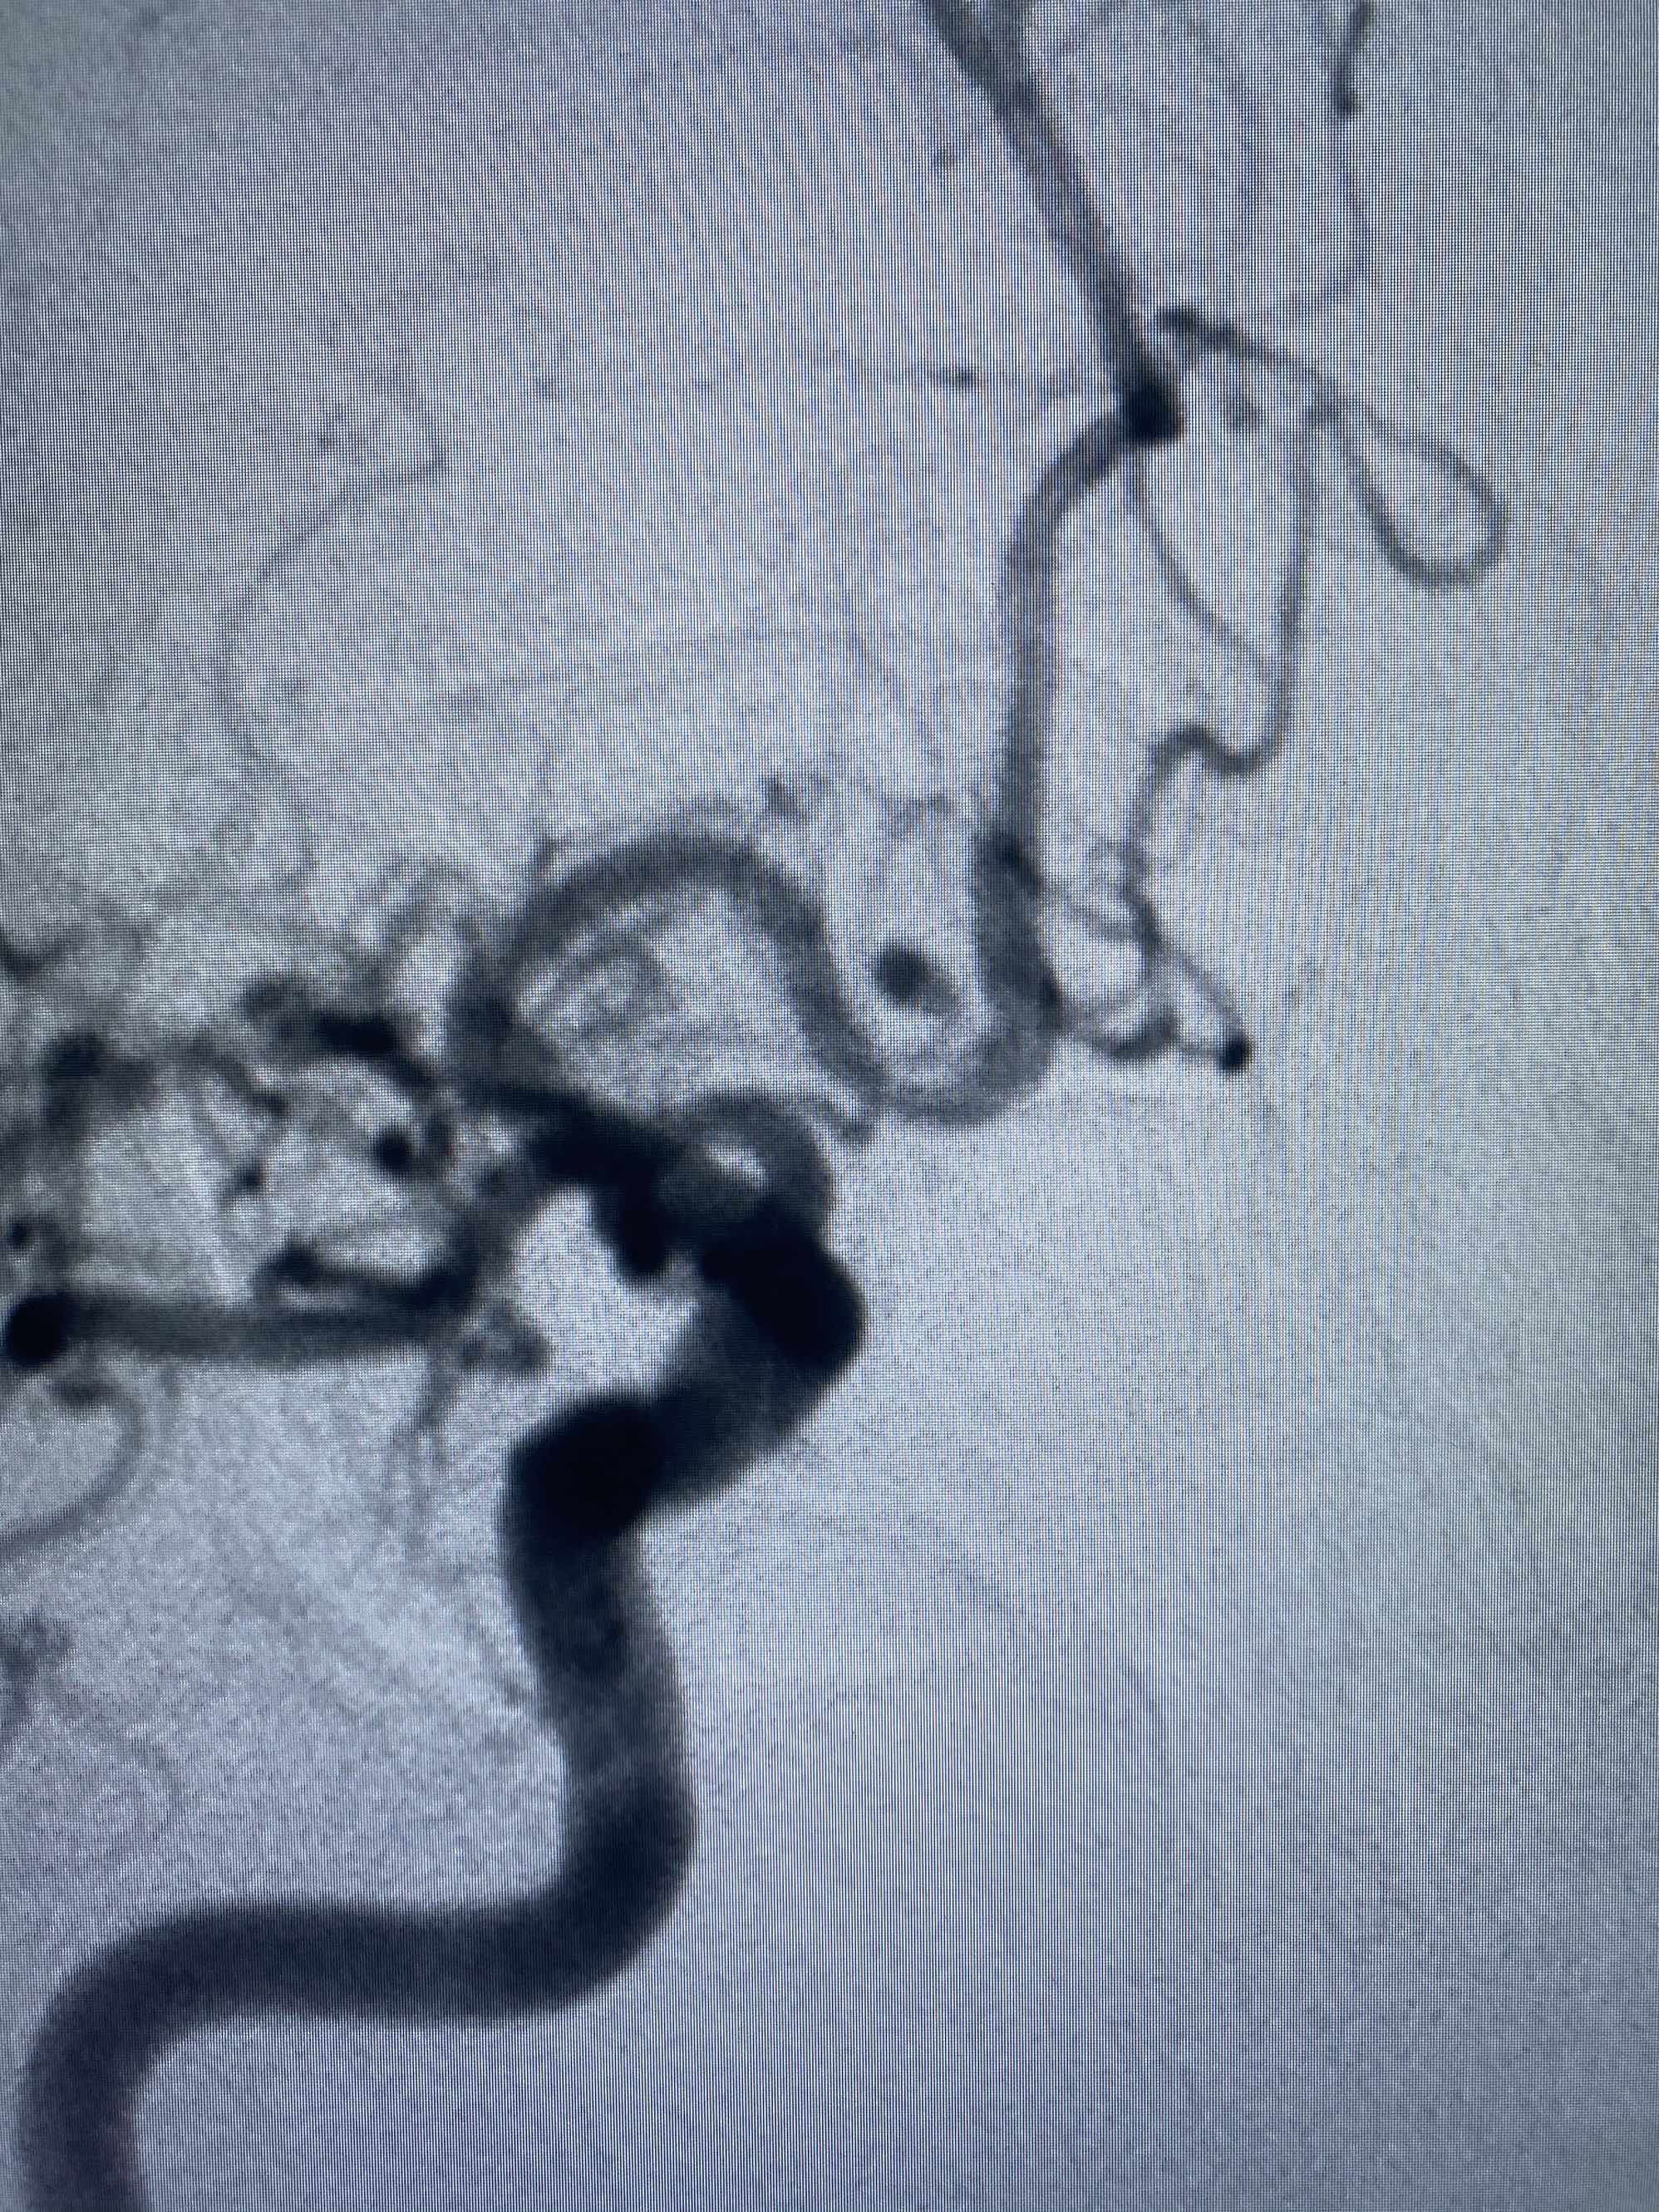

MLS,M79Y,sah,双侧MCA烟雾病,Heubner返动脉瘤,前交通段开窗,细支发出Heubner返动脉,瘤颈细长,瘤颈口比微导管细,弹簧圈2mmx3cm“隔山打牛”填塞治愈,Heubner返动脉保留。

该患者术后2天观察神志清楚,四肢活动正常。

Heubner返动脉是由大脑前动脉A1末端发出的豆纹动脉,由于走形和A1段相反,故称Heubner返动脉,该动脉梗塞可能引起尾状核头梗塞,引起偏瘫和面瘫,便身震颤等症状。